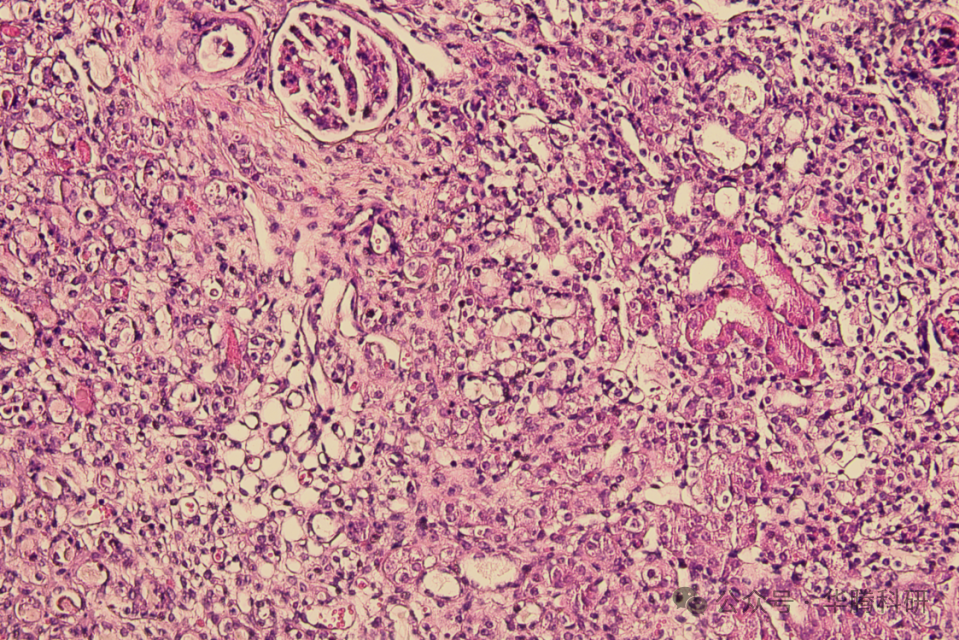

HE染色结果显示,假手术组小鼠肾小球结构清 晰、肾小管紧密排列,未见明显炎性细胞浸润。模 型组小鼠肾脏组织出现损伤,肾小球形态结构异 常,肾小管刷状缘缺失及小管扩张,临近小管细胞 与上皮细胞边界不明显,间质出现炎症浸润。

模型组40x